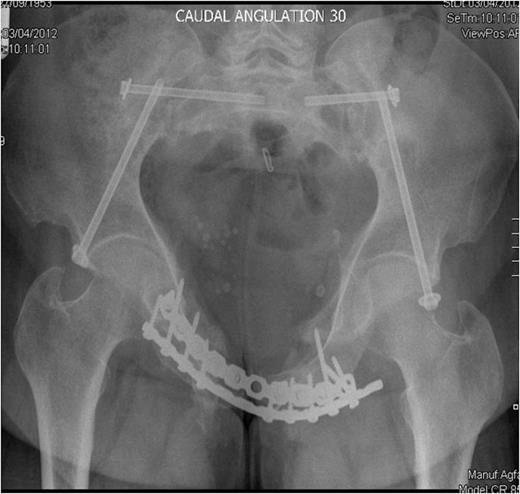

Post-operative recovery was uneventful. Bone and soft tissue biopsies showed no abnormalities. She was kept non weight bearing for 12 weeks. Subsequent dual energy X-ray absorptiometry scanning revealed mild osteopenia for which she is being managed medically. She began full weight bearing at 3 months post surgery. Final follow-up at 16 months demonstrated that the fractures had healed, and the patient was pain free and mobilising unaided (Fig. 3 & 4).

Outlet radiographs at 16 months post surgery demonstrating solid fixation and bony healing